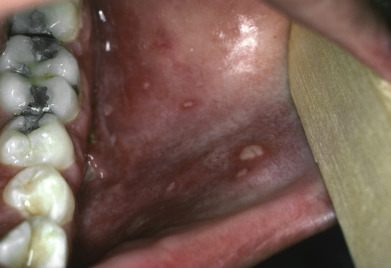

Primary conditions of the mucosal surfaces include changes to the tongue, such as median rhomboid glossitis or inflammation of the taste buds known as papillitis . Aphthous ulcers provide another example of a primary oral disease, and they are featured here with their classic round, shallow, white ulcers with surrounding bright red rims.